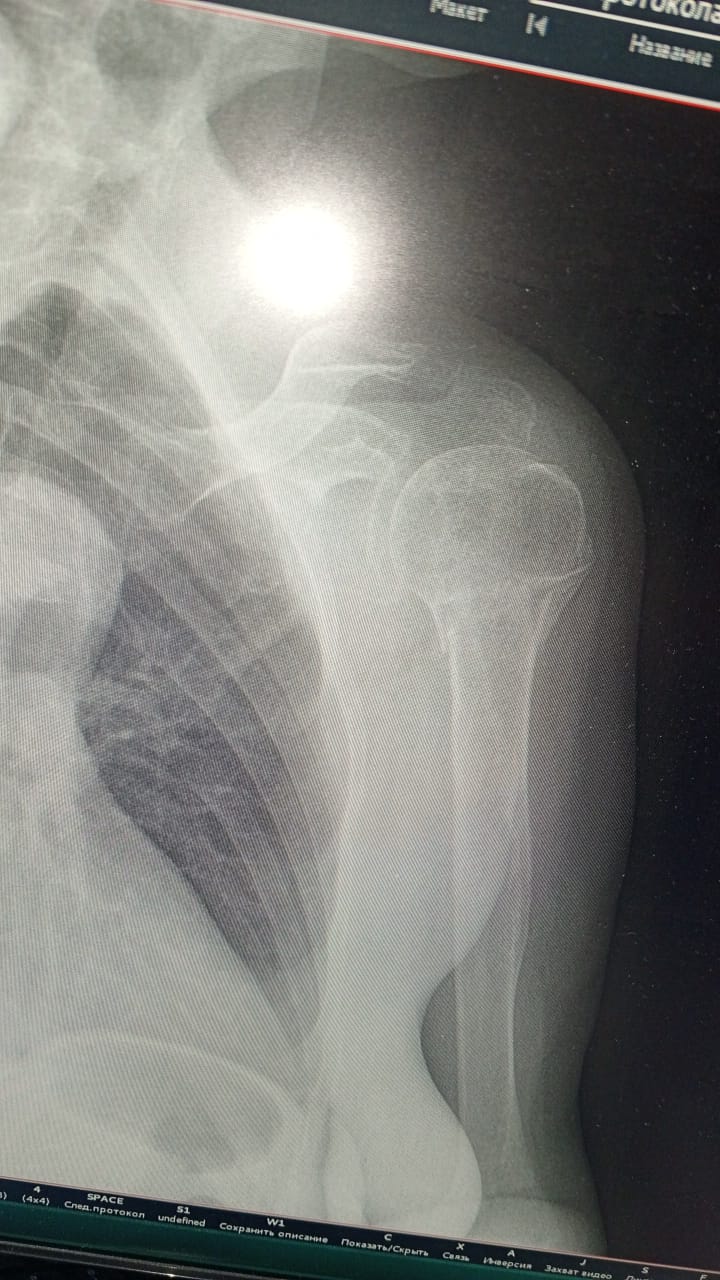

Закрытый перелом головки лучевой кости